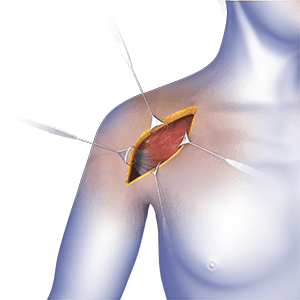

• Open Shoulder Stabilization

Open shoulder stabilization is a surgical procedure performed to treat a condition called shoulder instability.